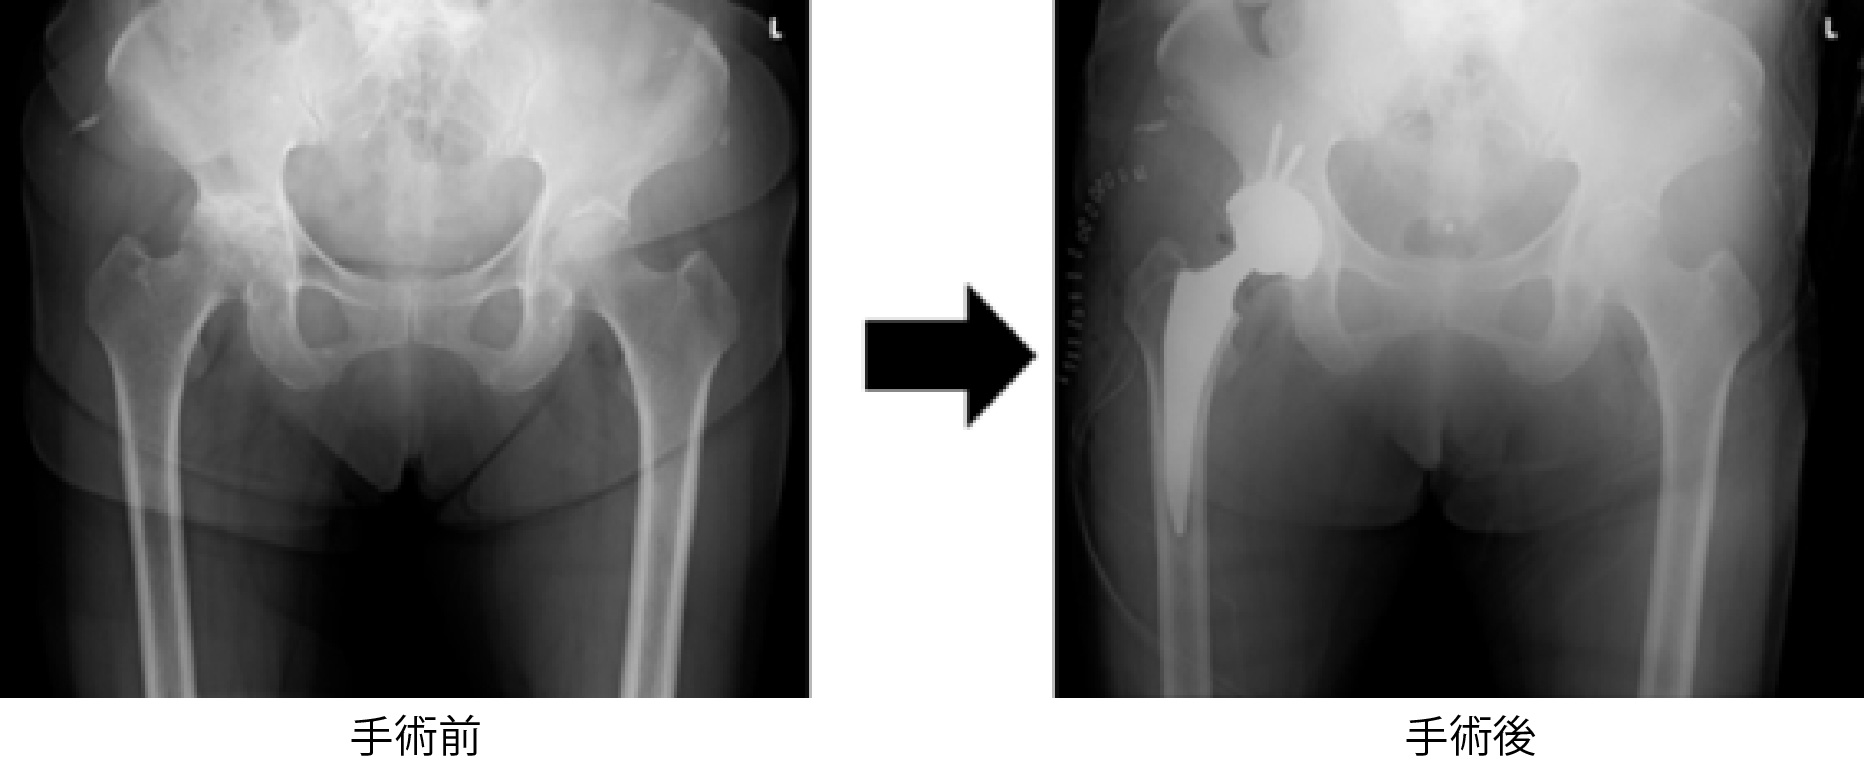

- 変形した関節を、金属やポリエチレンでできた人工関節に入れ替える手術です。

関節の変形による痛みがなくなり、歩行などの日常動作が改善されます。年齢や骨の形状、などによって骨セメントを使用するか、使用せずに骨に直接固定する方法があります。

変形性股関節症に対する全人工股関節置換術